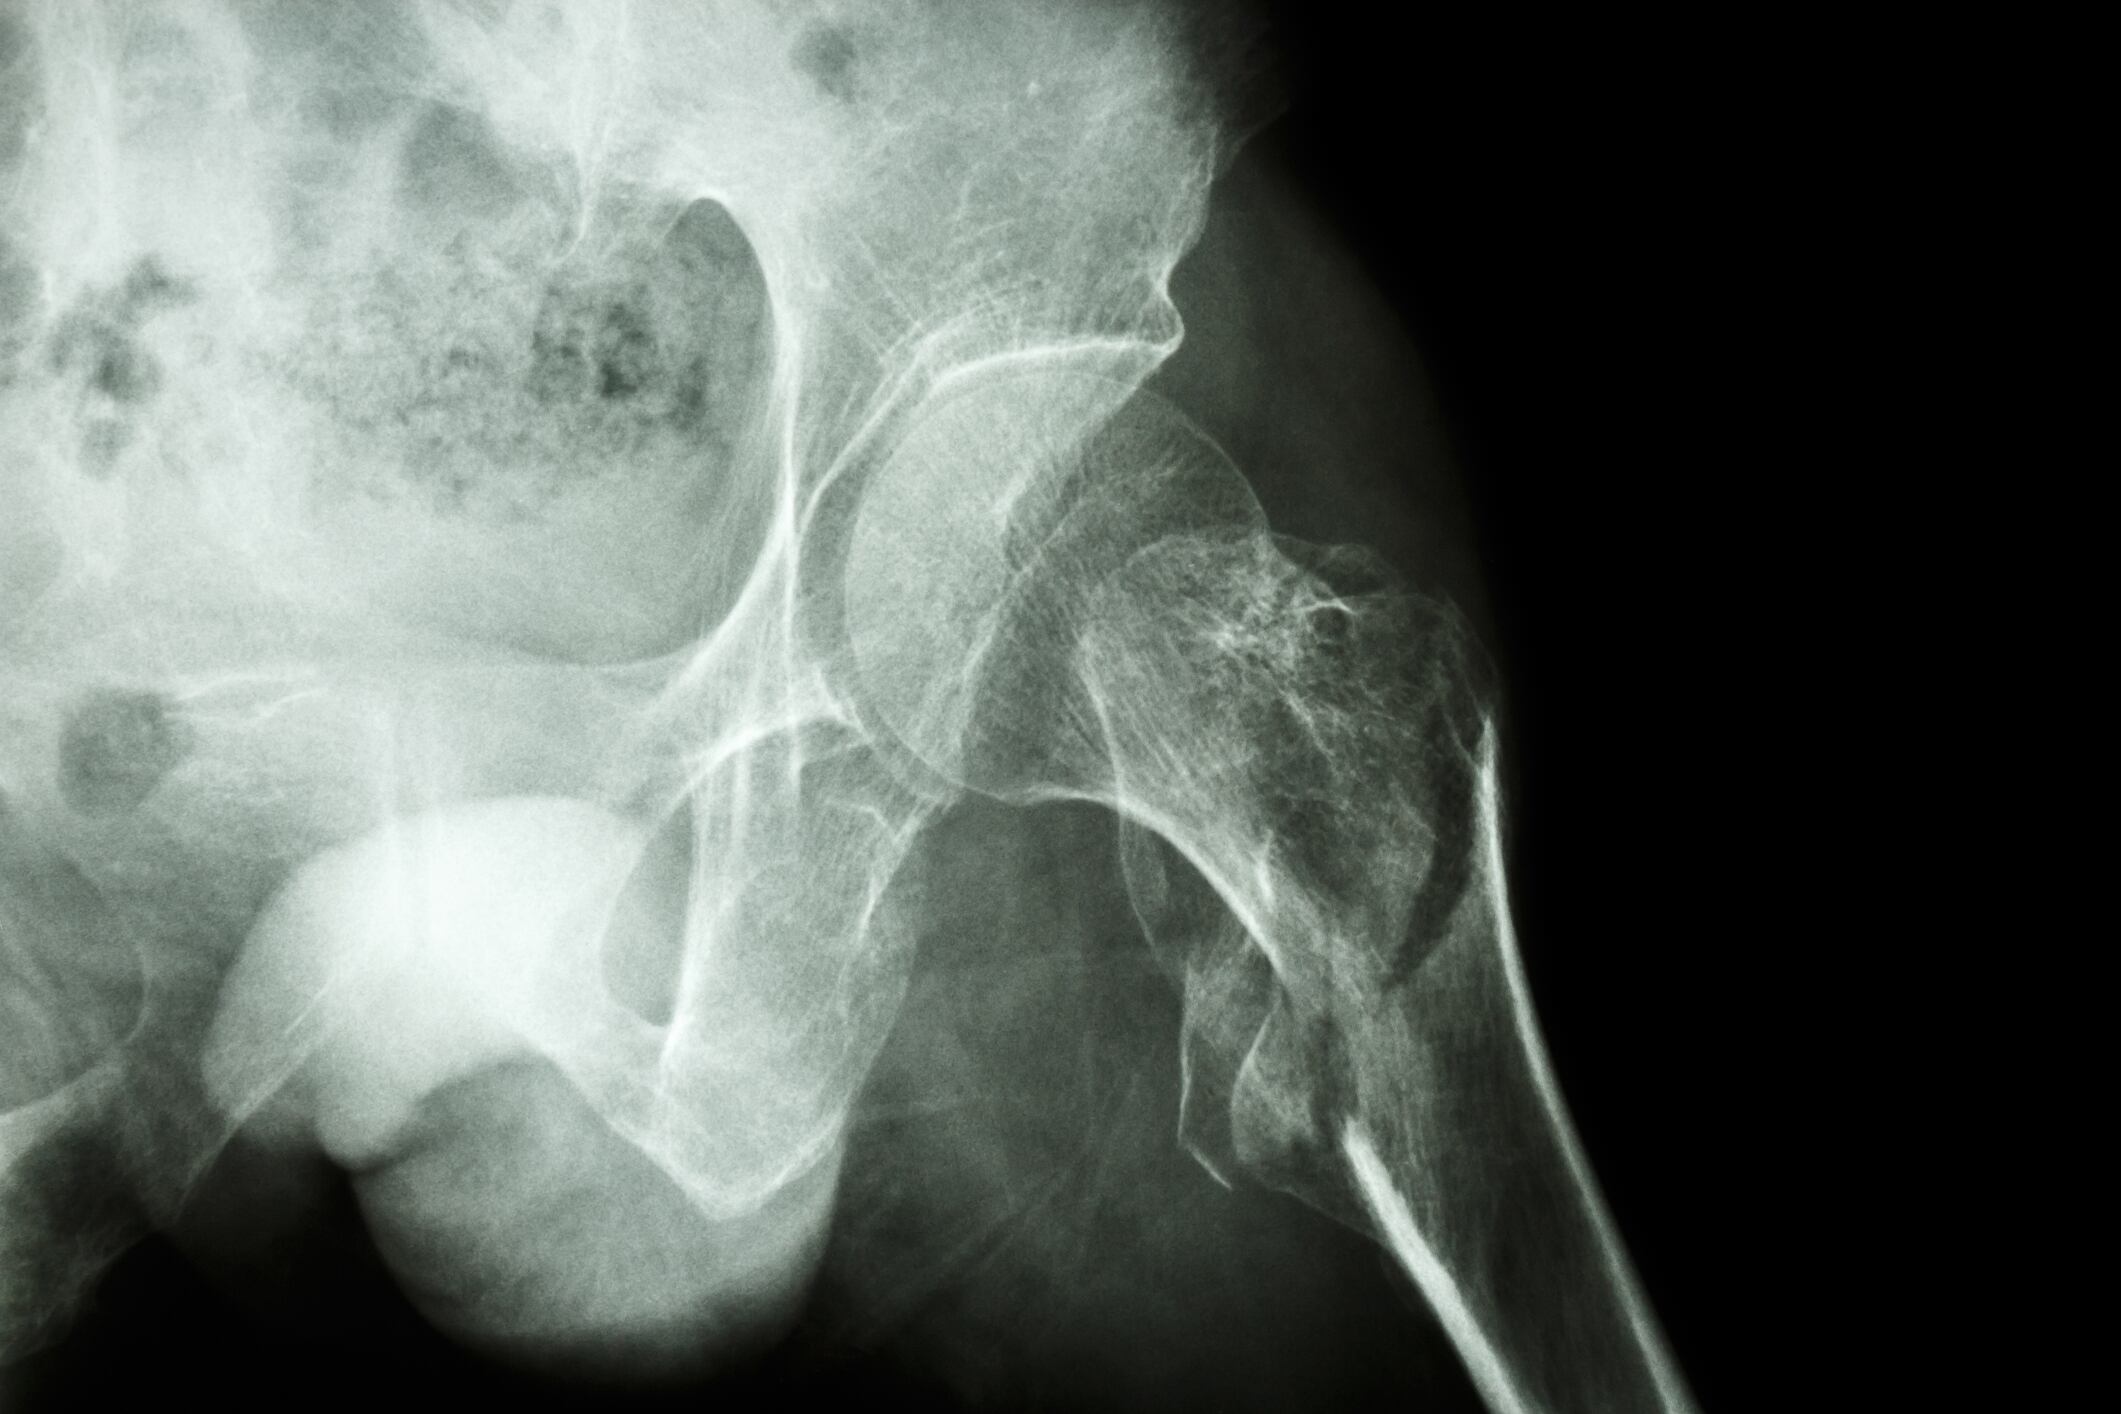

Specifically, an increase in BMD in the femur neck of about 4% was recorded in the probiotic group, while no changes were recorded in the placebo group.

“Considering the spontaneous loss of 1% to 2% BMD in postmenopausal women, the BMD results of this study could be meaningful,” wrote the researchers. “Furthermore, femur neck fractures could be more morbid than osteoporotic spine fractures, as the former frequently require surgical management.”